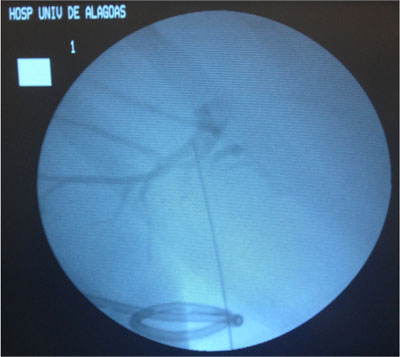

- Drenagem da Via Biliar e Dilatação da Estenose;

The main indications for a percutaneous treatment of a postoperative benign biliary stricture are:

(1) poor patient’s general condition that does not permit another surgical intervention,

(2) presence of altered anatomy that does not permit the endoscopic approach;

(3) septic status that requires a quick approach for decompression of the biliary tree.

Melhorar e manter a permeabilidade do ducto biliar, bem como prevenir a recorrência de estenose através de um procedimento minimamente invasivo.